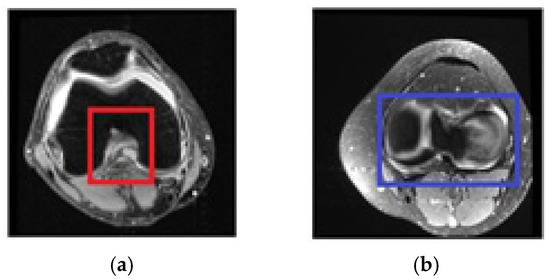

2.4. Selecting the Relevant Area

2.4.1. Selecting Relevant Areas on the Sagittal Axis

2.4.2. Selecting Relevant Regions on the Coronal Axis

2.4.3. Selecting Relevant Regions on the Axial Axis